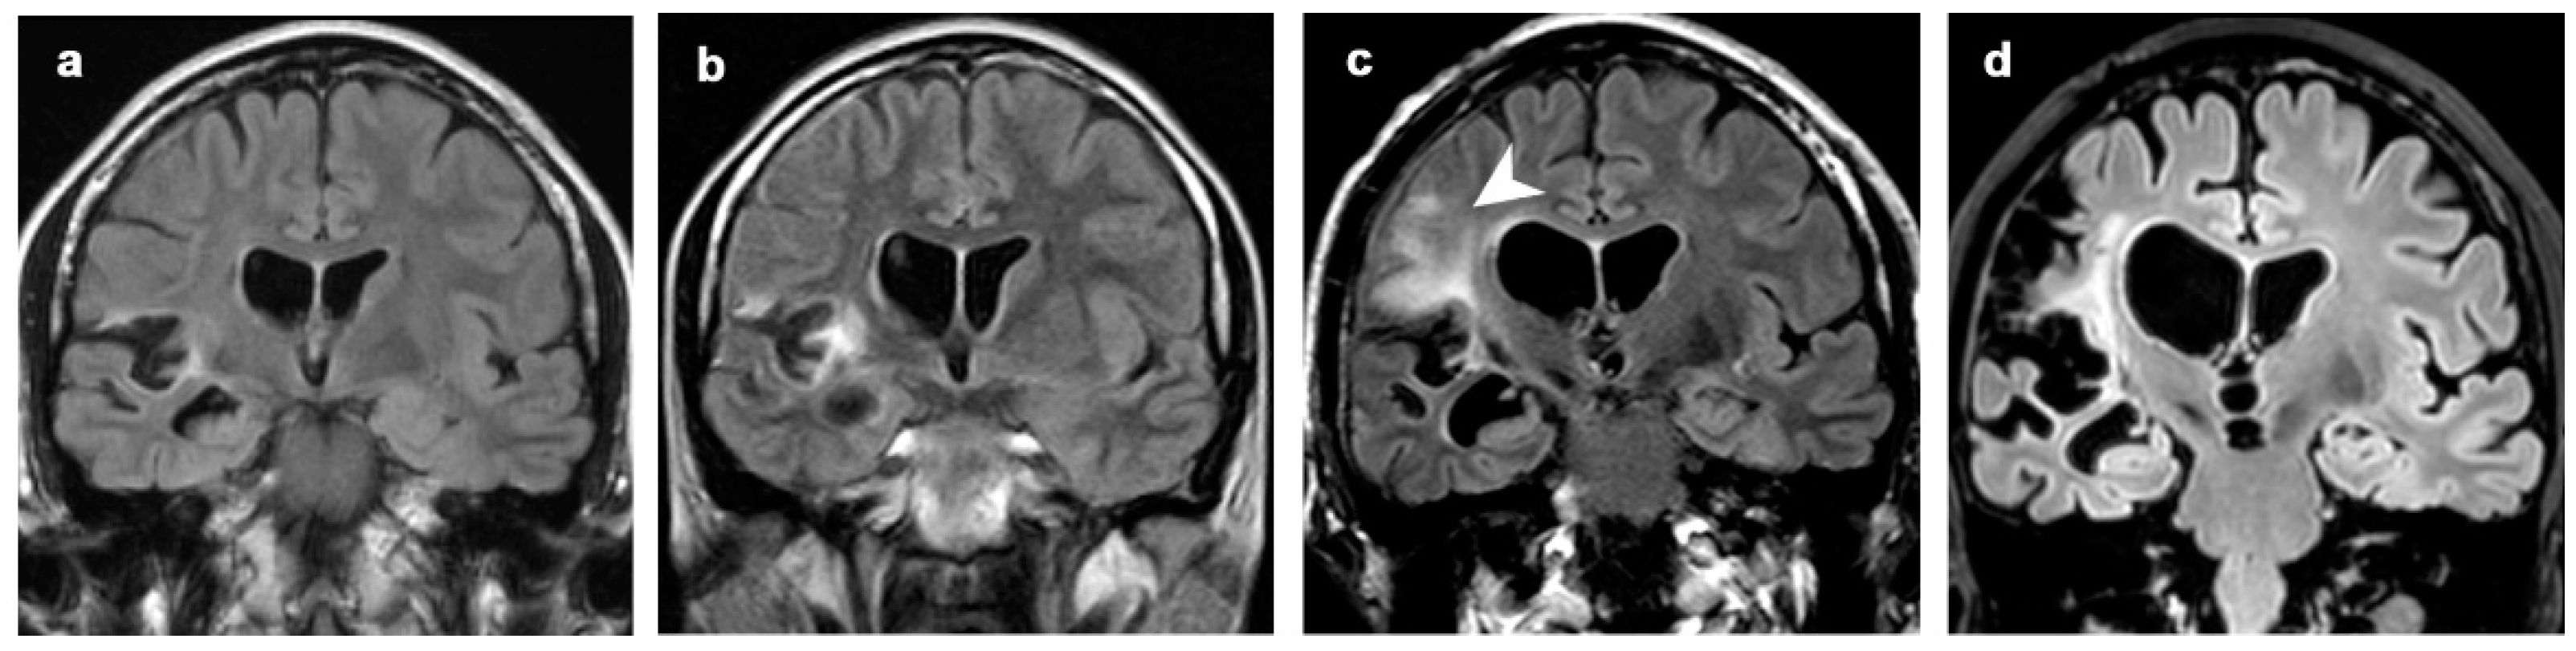

3.1. Atrophic Changes

3.2. Changes in Signal Intensity